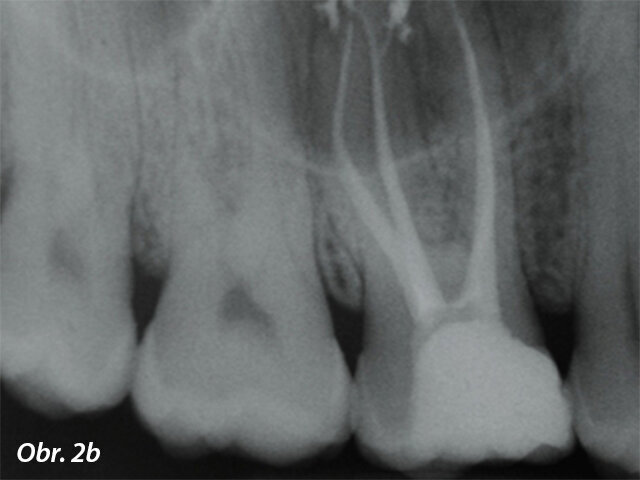

In vitro a ex vivo studie ukázaly přítomnost bakterií v dentinových tubulech a cementu i po endodontickém ošetření, což zdůrazňuje, že cíl absolutní dezinfekce kanálku není pravděpodobně dosažitelný pouhým čištěním a opracováním.Plnění opracovaného kořenového kanálku je následným krokem v endodontické terapii a slouží jako prevence bakteriální reinfekce zubu a periapexu. Většina obturačních systémů v endodontické terapii je složena ze základního materiálu a sealeru. Sealer by měl nejen vyplnit mezery mezi základním materiálem a stěnou kořenového kanálku, ale také povrchové nerovnosti systému kořenových kanálků (jako jsou laterální kanálky a isthmy), aby bylo dosaženo pevného utěsnění (obr. 2a, b).K překonání problému bakteriální persistence v systému kořenových kanálků byly postupně vyvíjeny a uváděny na trh materiály s antibakteriálními vlastnostmi. Antibakteriální povaha sealeru je cenná kvůli vyššímu procentu fakultativních anaerobů v případech selhání léčby kořenových kanálků. Objevilo se několik sealerů na bázi pryskyřic a MTA, u kterých výrobci tvrdili, že mají schopnost zničit bakterie ponechané v dentinu kořenových kanálků, avšak literatura ukázala, že antimikrobiální sealery (především sealery na bázi pryskyřice) jsou efektivnější, když jsou čerstvě namíchány, a jejich aktivita se snižuje po ztuhnutí,a tedy se na ně nelze spoléhat v prevenci reinfekce v průběhu delšího období.

Úspěšná terapie je, když jsou plnicí materiály schopny pevně utěsnit prostor kořenových kanálků, a to i v případě více výstupů